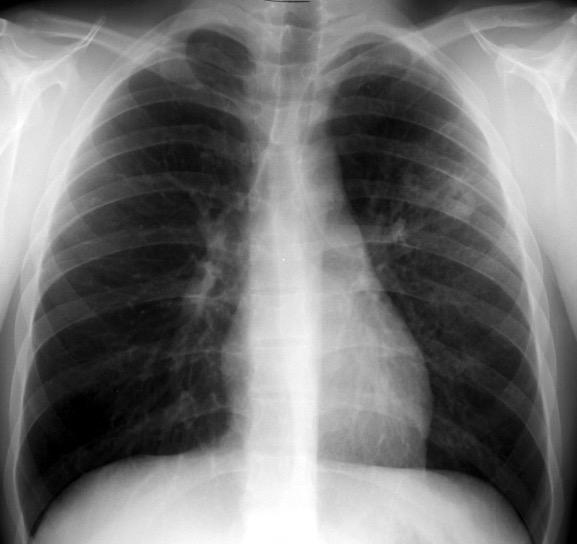

BRONCOGRAMA AÉREO

Bronquios rellenos de aire sobre un fondo de pulmón sin aire debido a:

a) Reabsorción en atelectasia

b) Reemplazamiento en neumonía, hemorragia, etc.

c) Combinación de ambas

d) Expansión intersticial exagerada

Fleischner FG. The visible bronchial tree; a roentgen sign in pneumonic and other pulmonary consolidations. Radiology 1948

Hansell DM et al. Fleischner Society: Glossary of Terms for Thoracic Imaging. Radiology 2008

Neumonía por Neumococo. (Broncograma visible a través de derrame pleural)

Neumonía

Edema pulmonar

Atelectasia no obstructiva

Hemorragia

Infarto

Ca.

”broncoalveolar”

Linfoma

“Normal” (espiración)

Walker CM et al. Imaging Pulmonary Infection: Classic Signs and Patterns. AJR. 2014 Collins J. CT signs and patterns of lung disease. Radiol Clin N Am 2001